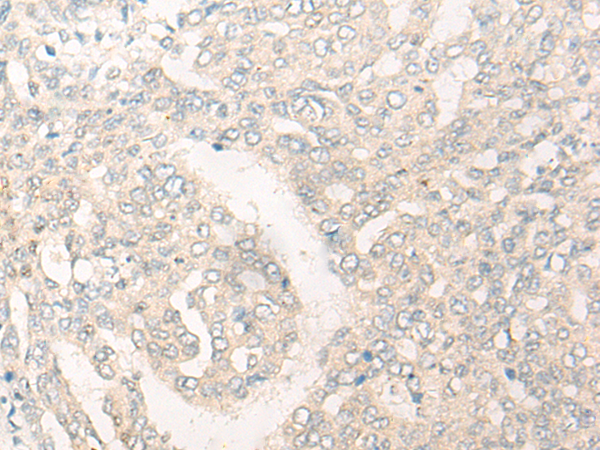

分类: 科研抗体货号: P13239别名:应用: IHC反应种属: Human